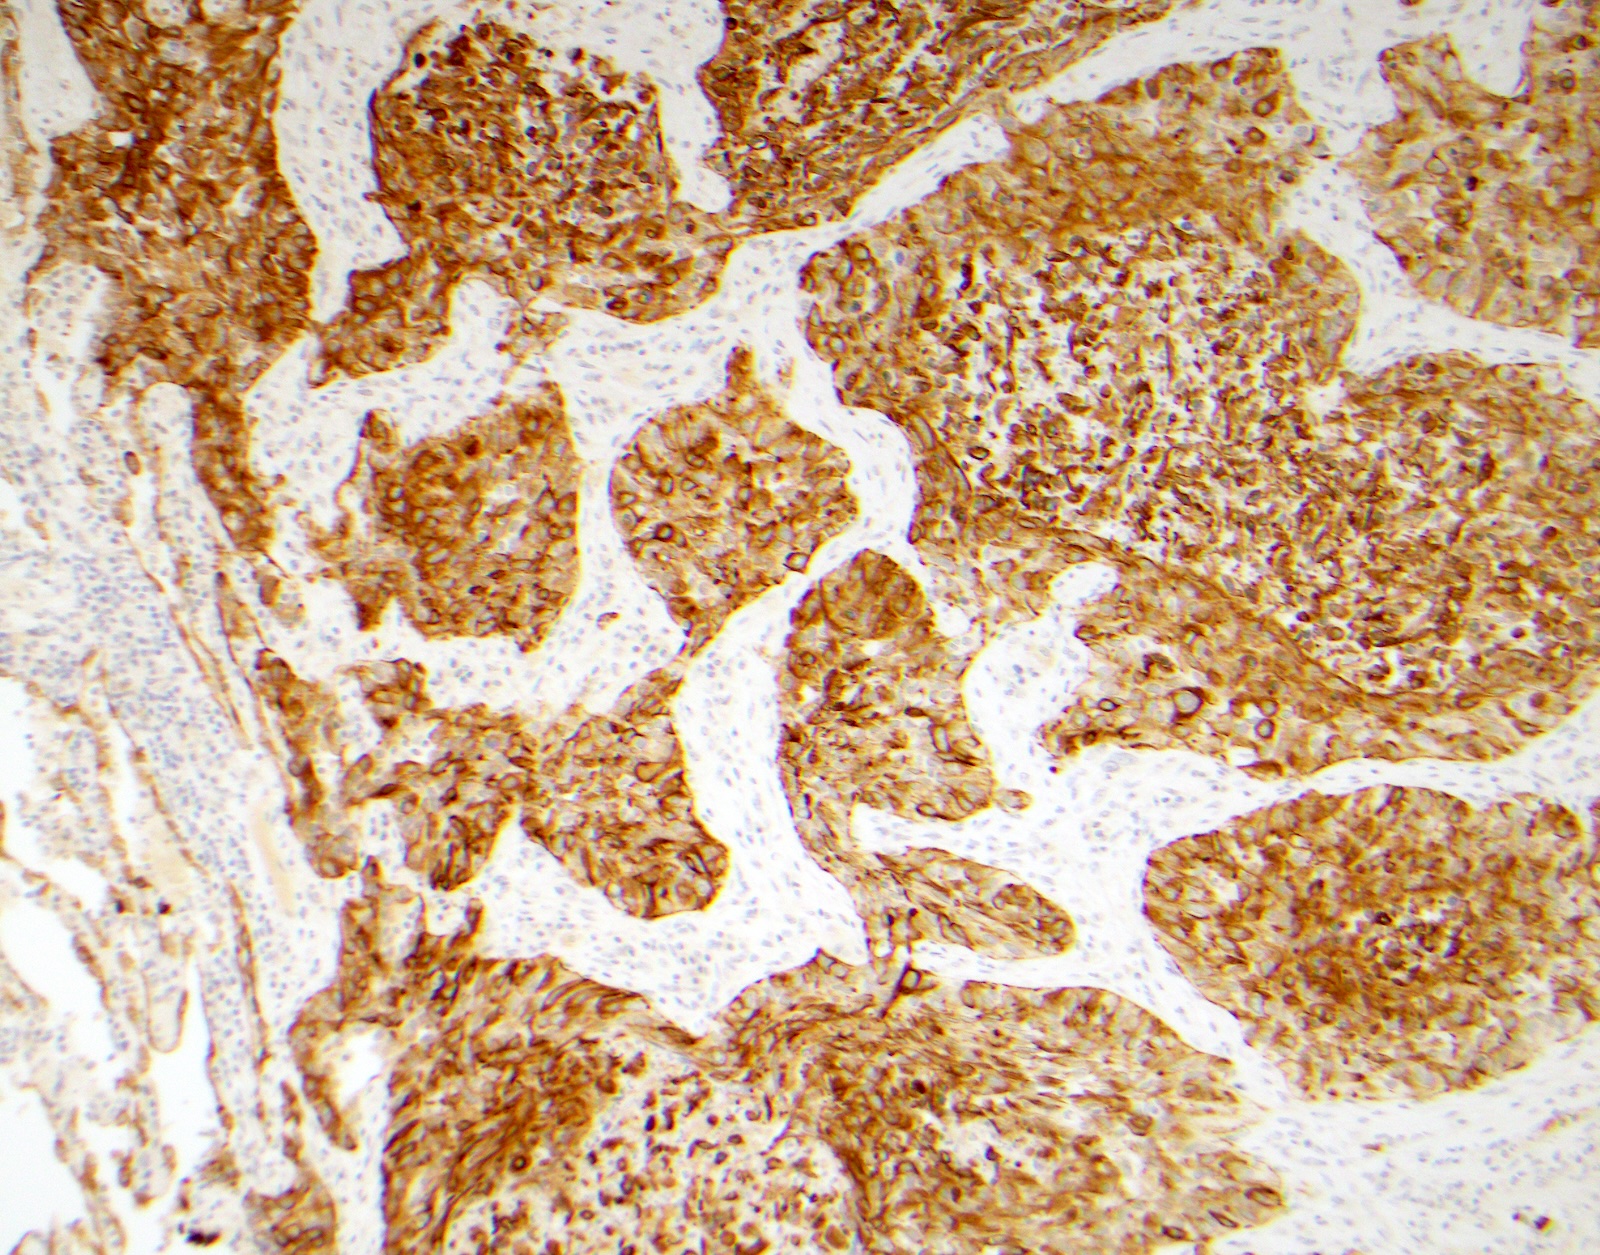

Microscopic (histologic) images

Contributed by Surekha Bantumilli, M.D. and Dimitri G. Trembath, M.D., Ph.D.

- Prostatic basal cell hyperplasia (Hum Pathol 2003;34:462)

- Identification of the basal cell layer in prostate tissue in the determination of carcinoma

Practice question #1

A 65 year old man presents with elevated prostate specific antigen (PSA) and undergoes a prostate biopsy, stained with high molecular weight cytokeratin (HMWCK) (shown above). What is the most likely interpretation of this staining pattern?

- Benign prostate tissue

- Benign seminal vesicle

- High grade prostatic intraepithelial neoplasia

- Prostatic adenocarcinoma

- Urothelial carcinoma

Practice answer #1

A. Benign prostate tissue. The basal layer of benign prostate glands will stain with high molecular weight cytokeratin. Answer D is incorrect because staining will be lost on prostatic adenocarcinoma. Answer C is incorrect because high molecular weight cytokeratin staining can be present in high grade prostatic intraepithelial neoplasia but is not diagnostic by itself for this entity. Answers B and E are incorrect because the glandular appearance outlined by the high molecular weight cytokeratin staining is not consistent with either seminal vesicle or urothelial carcinoma.